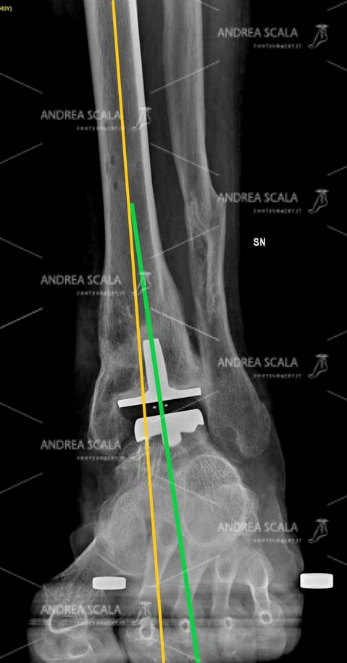

La RXgrafia sottocarico mette in evidenza l’artosi di caviglia dopo una grave frattura. La Rx grafia mostra che la frattura ha spostato l’ASSE BIOMECCANICO dall’ASSE ANATOMICO. Questo spostamento va attentamente calcolato prima di impiantare la protesi della caviglia. Si vede che il paziente ha già subita la frattura del perone dalla quale è guarito. Non si vede il motivo scientifico perché si dovrebbe di nuovo rompere il perone e rifare un danno per l’organismo per impiantare la protesi di caviglia.

La RXgrafia sottocarico mette in evidenza l’artrosi di caviglia dopo una grave frattura. La Rx grafia mostra che la frattura ha spostato l’ASSE BIOMECCANICO dall’ASSE ANATOMICO. Questo spostamento va attentamente calcolato prima di impiantare la protesi della caviglia. Si vede che il paziente ha già subita la frattura del perone dalla quale è guarito. Non si vede il motivo scientifico perché si dovrebbe di nuovo rompere il perone e rifare un danno per l’organismo per impiantare la protesi di caviglia.

La RXgrafia eseguita nelle stesse condizioni mostra l’impianto della protesi di caviglia. In questo caso particolare è stata scelta una protesi con il fittone tibiale che è stato allineato secondo L’ASSE BIOMECCANICO allo scopo di assicurare alla protesi un funzionamento migliore e una vita più lunga.